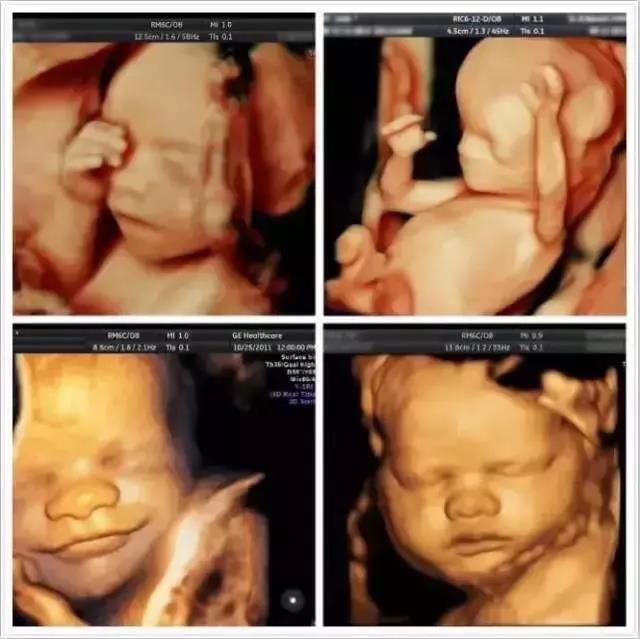

宝妈感受着宝宝在肚子里天天的长大,呆在肚子里那么永了,就会生出想见你的情绪,迫不及待的想见你!想见你肉呼呼的小手, 软绵绵的小肚子,宝妈也想和宝宝来场约会吧~

通过胎儿系统超声,

宝爸宝妈们还可提前看到宝宝的样子,

现在就让我们瞧瞧

那些年,

艾玛妇产抓拍到的胎宝宝“可爱萌”瞬间

吃手手

动动

跺跺脚

吐舌头

孕期,通过高分辨率的彩色多勒普超声诊断仪,医生可以看到胎儿各器官的解剖结构,对胎儿发育情况进行筛查。同时通过高清晰度的图片成像,宝爸和宝妈能看到深居“宫”中小宝贝的秀容和举动。这个冬天,和宝宝来场穿越时空的约会吧!